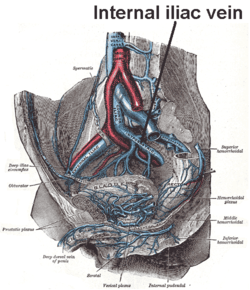

The veins of the right half of the male pelvis. | |